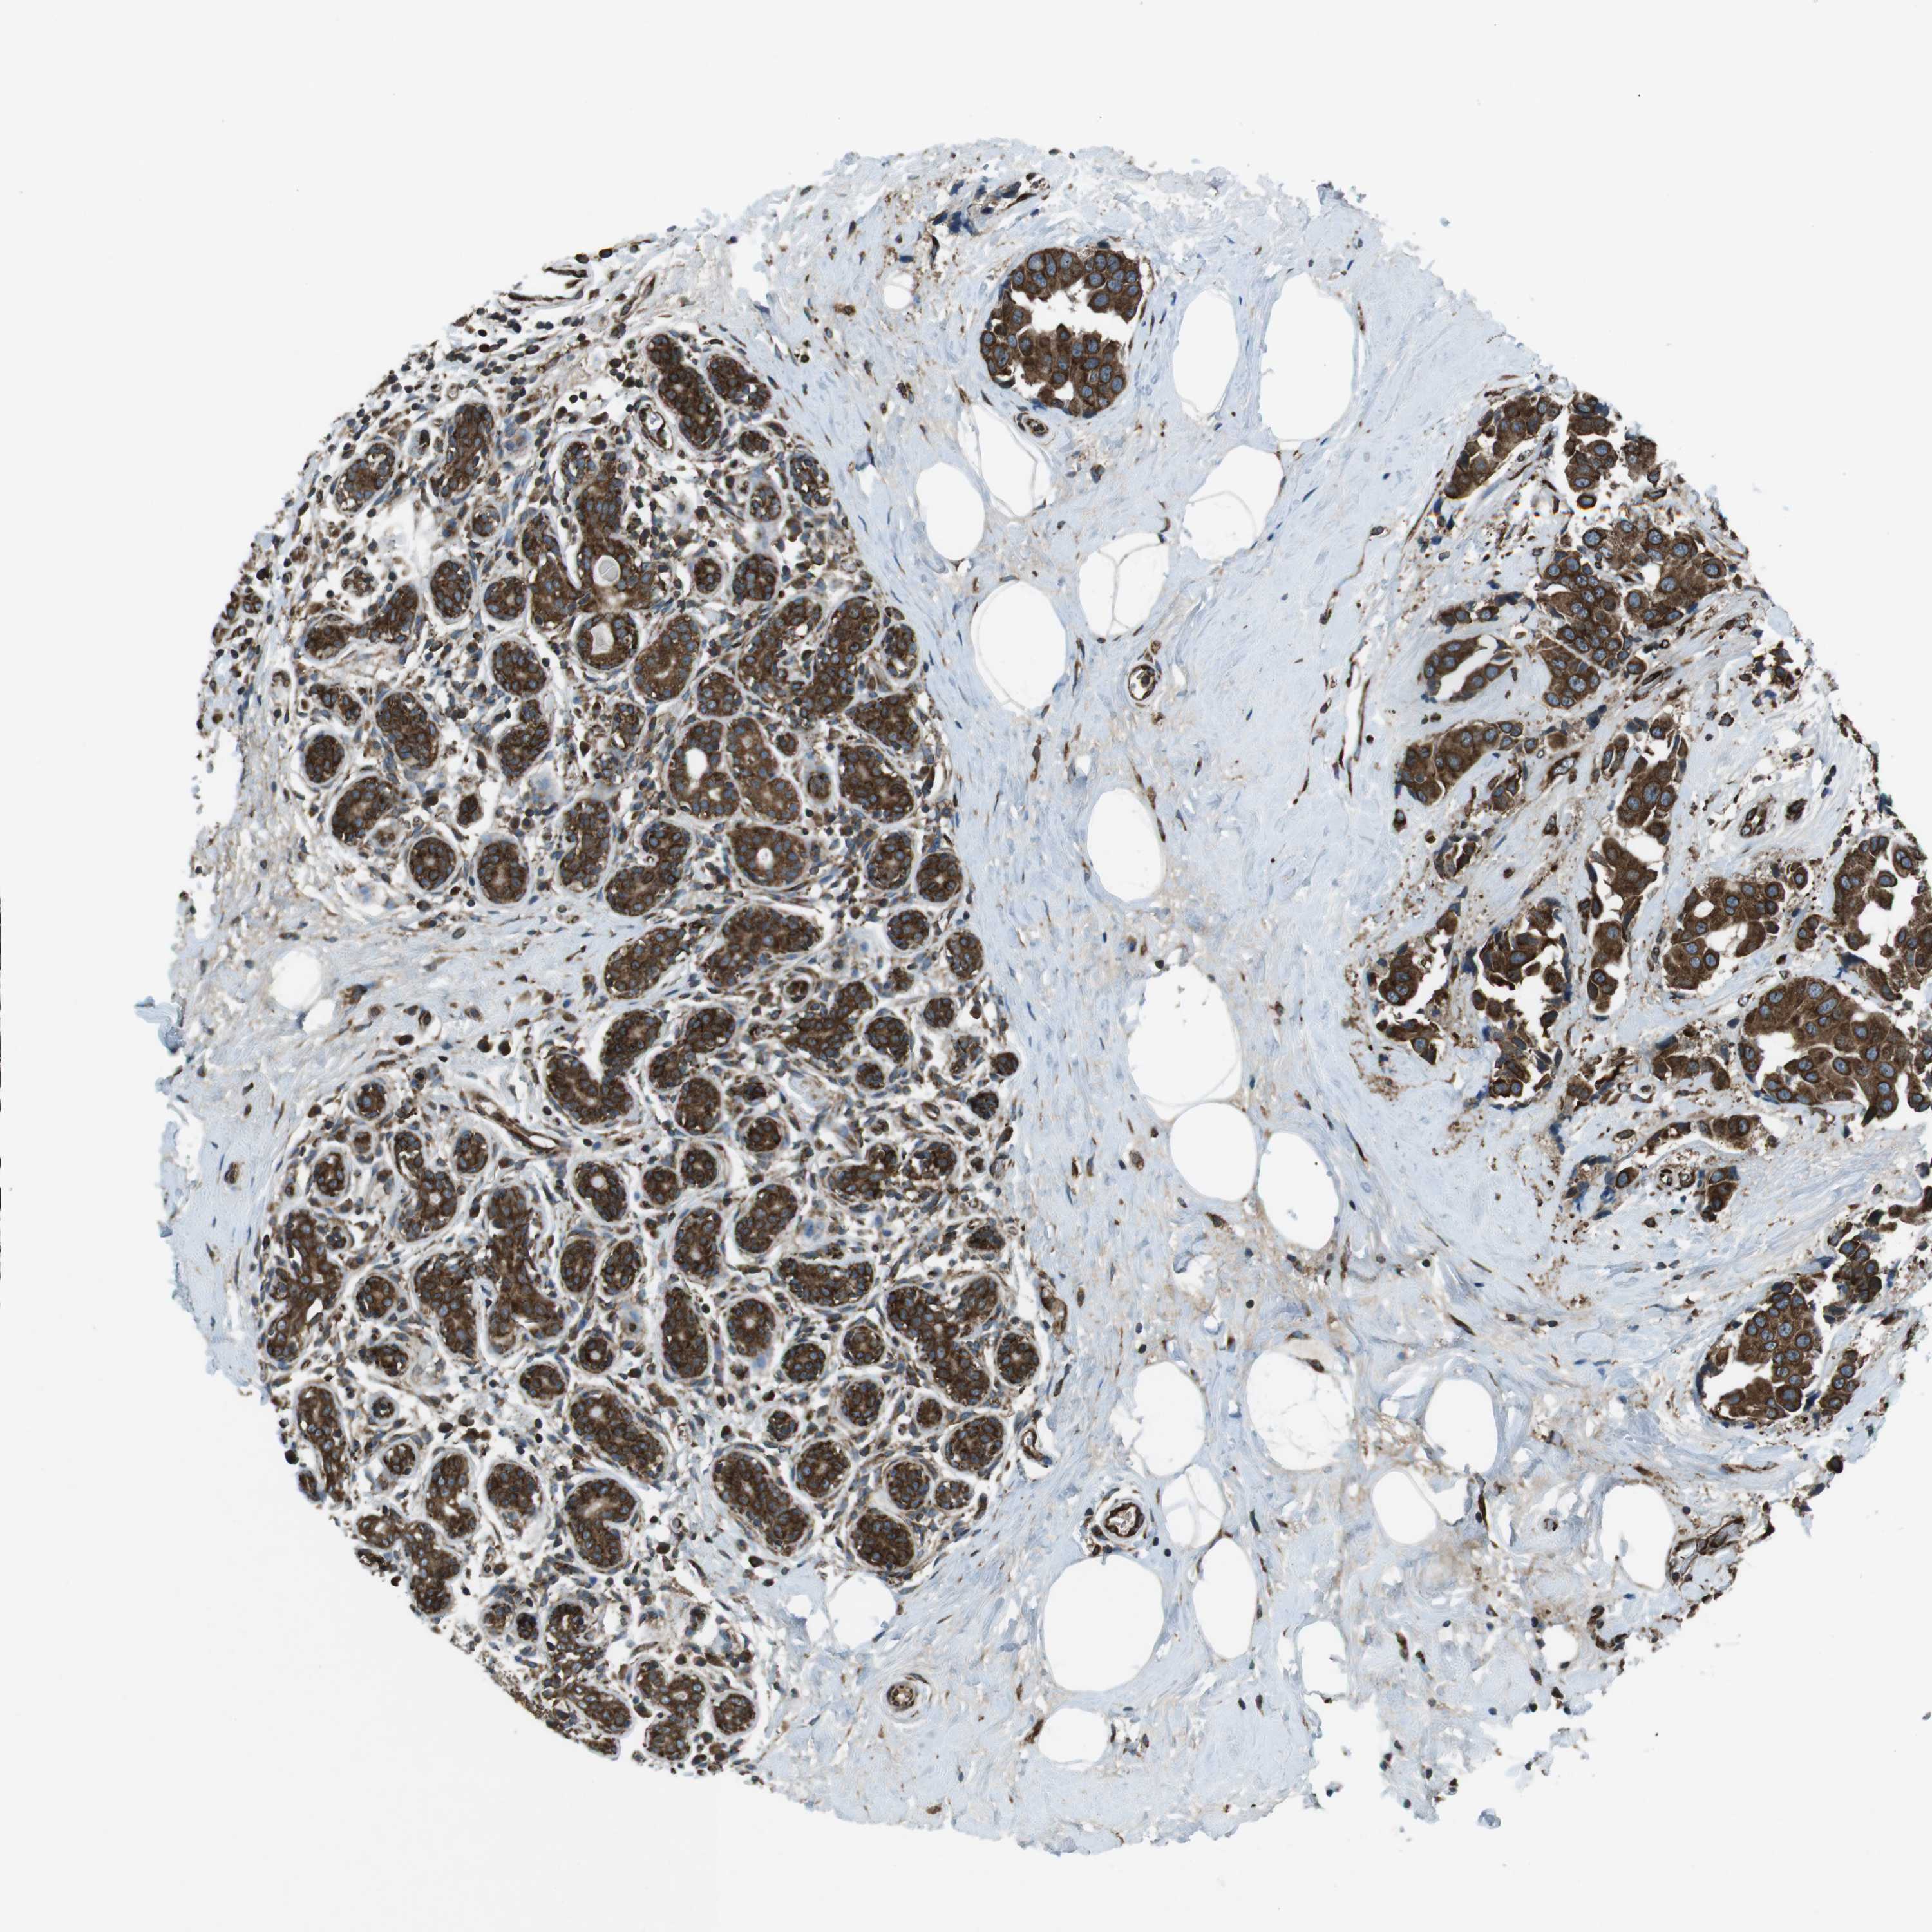

CANCER BREAST CANCER Show tissue menu

BRCA TCGA BRCA VALIDATION PROTEIN EXPRESSION